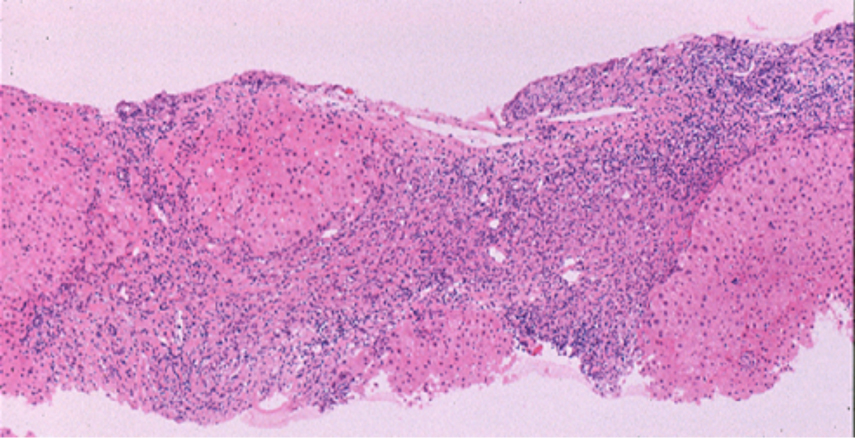

肝生検組織像(1)

門脈域にリンパ球を主体とした単核球細胞浸潤と小葉間胆管の障害像および肉芽腫形成を認める。